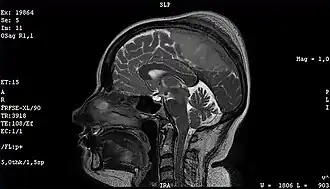

Опухоль

О́пухоль (др.-греч. -ομα, лат. tumor), также новообразование, неоплазия, неоплазма — патологический процесс, представленный новообразованной тканью, в которой изменения генетического аппарата клеток приводят к нарушению регуляции их роста и дифференцировки.